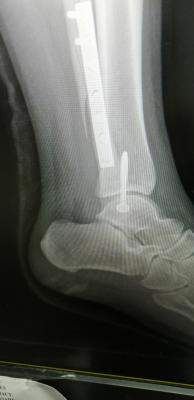

Hey guys, I wonder does anyone have the same experience with me before. I broken my right leg fibula bone and my ankle was fractured last year April and undergo multiple surgeries. I have one plate and some screws on my fibula bone and same on my ankle.

QUOTE(vincabby @ May 10 2019, 09:37 AM) hi. hope the surgery was a success. for the next one month u will need crutches for sure. Once the cast is out, then you can slowly put weight but you won't find a lot of movement till at least 6 months. i am putting it longer so you wont pressure yourself and risk a bad healing period. hey. ya surgery was a success. have one metal bar and 2 screws. I bought the old ppl tongkat. easier to use than crutch. my friend lend me his when he was suffering from knee injury. once I can put some weight, I'll use those crutch. I find it tough to balance on crutches, so I bought old ppl tongkat.

QUOTE(vincabby @ May 10 2019, 02:10 PM) that might not be comfortable in the long run. try the ones where u put your whole arm through the support for the crutch instead of under armpits. those are tiring. if u are using the old man ones, guess u should spend more time sitting and resting. I have both. The old one, and whole arm. I didn't buy under armpits. Unstable and dangerous to use. The old ppl one is for stability. Once my feet can hit the ground, I'll use the whole arm one. My friend lend the whole arm to me while I bought the old ppl one. I don't expect myself to move so much already. Just in bed, and during meals. And some leg day exercise to boost my thigh energy. QUOTE(abuyon @ May 10 2019, 02:13 PM) u might have osteochondral injury of your ankle cartilage..that is y u have bad pain after bad fractured... Mai scare me leg. My scan results are out. Ligament tendon all good. Just bone broken and one part dislocated. Broken part all screws. Dislocated, screwed back to strengthen. Attached thumbnail(s)